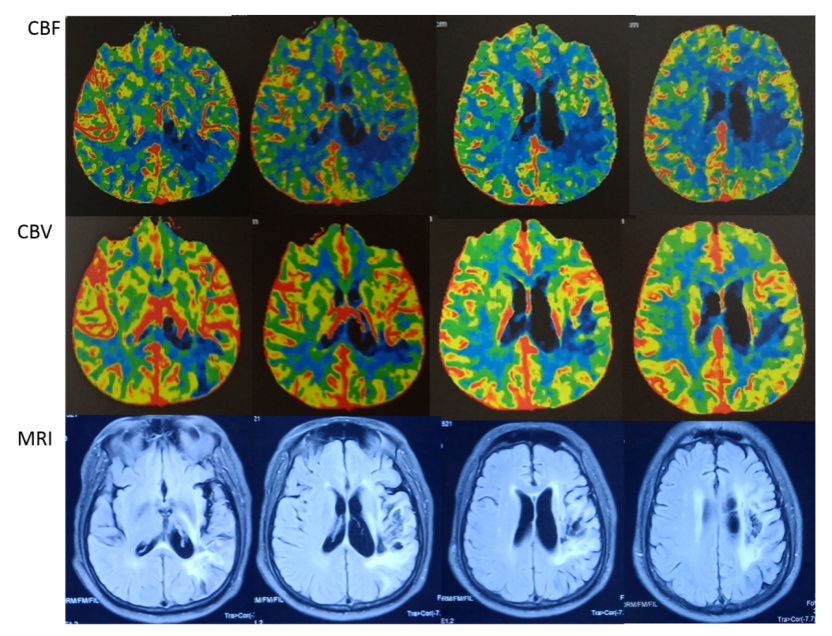

入院影像评估:

影显示左侧MCA M1段重度狭窄,右侧椎动脉V4段近闭塞,左侧VA PICA以远闭塞。基底动脉中段中重度狭窄,左侧AICA显影浅淡,右侧AICA不显影。左侧PCA不显影。

T2 Fliar 图像提示颞顶区域陈旧梗死灶,梗死区域多位于左侧大脑中动脉穿支区域,小脑半球,脑干区域未见明显缺血病灶。

左侧大脑中动脉供血区域,除陈旧梗死区域外,CBF轻度下降,CBV未见明显变化,提示局部部分代偿。